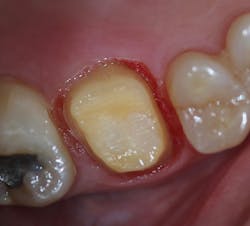

Upon achieving local anesthesia, an impression was made for provisional crown fabrication using a triple tray and monophase VPS impression material (V-Posil Mono Fast , Voco; figure 9). The tooth was then prepared for a crown using a flowable, dual-curing, nano-hybrid core build-up material (Grandio Core Dual Cure, Voco; figure 10).

Figure 9: Impression for provisional crown fabrication

Figure 10: Tooth preparation